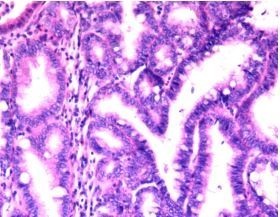

诊断: 胆总管囊肿 治疗:全麻下手术治疗。术中探查,见胆囊大10x6x4cm,肝门部可触及肿大胆总管,直径约6cm,向下延续到胰腺段,切除胆囊,于肝总管横断,向下剥离胆总管,直至胰腺段,仔细分离胆总管与胰腺,避免胰腺组织破碎,直到胆总管变细部位,切断之,远端缝扎,继续行肝管空肠Roux-en-Y吻合术。术后病理胆总管绒毛管状腺瘤,伴高级别上皮内瘤变,有恶变趋势,慢性胆囊炎。